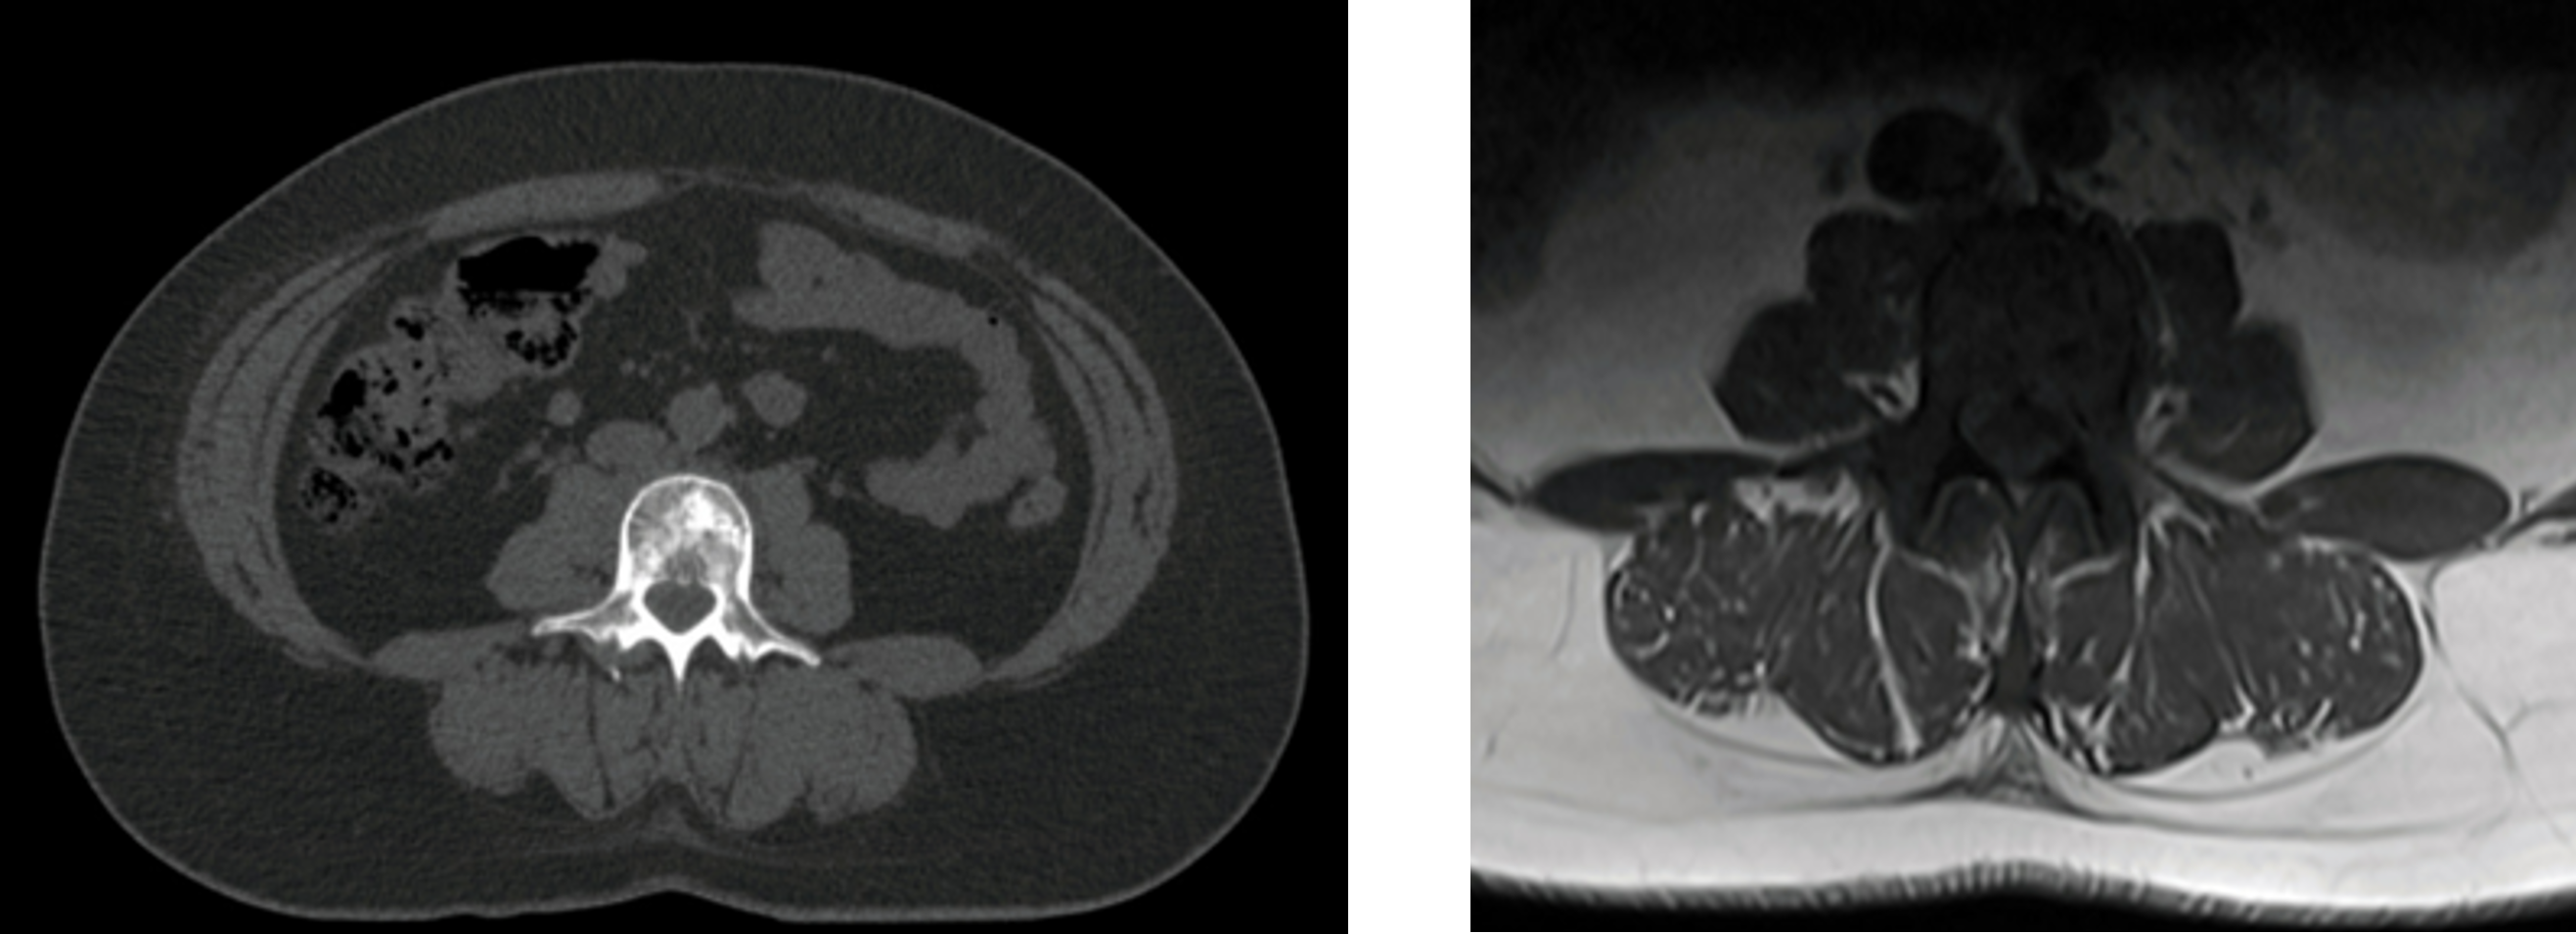

By the next presentation of lumbar pain in July 2022, Capecitabine was added to her systemic treatments. A whole spine MRI showed L3 metastasis at the level of her new lumbar pain.

Challenges of presentation and choice of treatment

The patient was offered 8 Gy in one fraction or 20 Gy in five fractions on the NHS, but made an appointment with her Clinical Oncologist Consultant, Dr Luis Aznar-García, at GenesisCare for a second opinion. Having reviewed her case and MRI scan, the patient was advised that SABR treatment, based on evidence from a randomised clinical, has shown better pain control with a SABR treatment of 24 Gy in two fractions than palliative conventional radiotherapy at three and six months.

Figure 2: Axial CT planning scan

Figure 3: Axial MRI planning scan